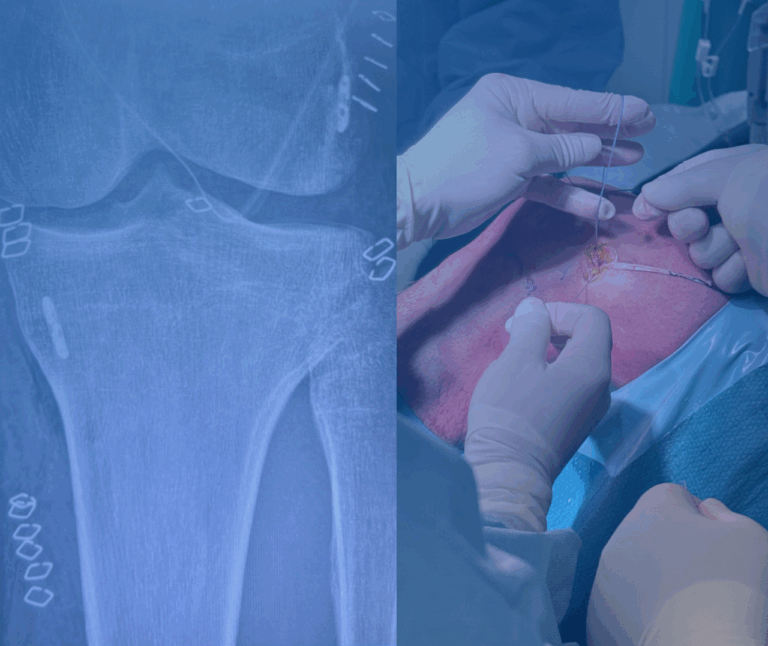

Gonartrosi – Intervento di protesi di ginocchio